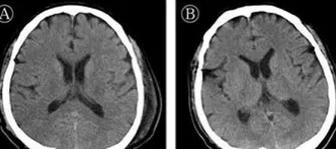

北京地坛医院首次证实:新冠病毒攻击中枢神经系统2020年03月05日 08:25:10